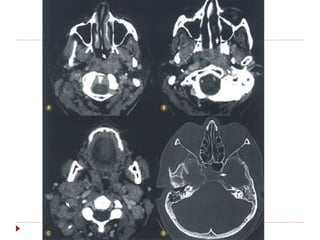

 TC contrastada é o método de escolha (1-3 mm).

 RM  T1, T2, STIR, gadolíneo, supressão de

gordura, difusão.

Nasofaringe  TC contrastadaé o método de escolha (1-3 mm).  RM  T1, T2, STIR, gadolíneo, supressão de gordura, difusão.